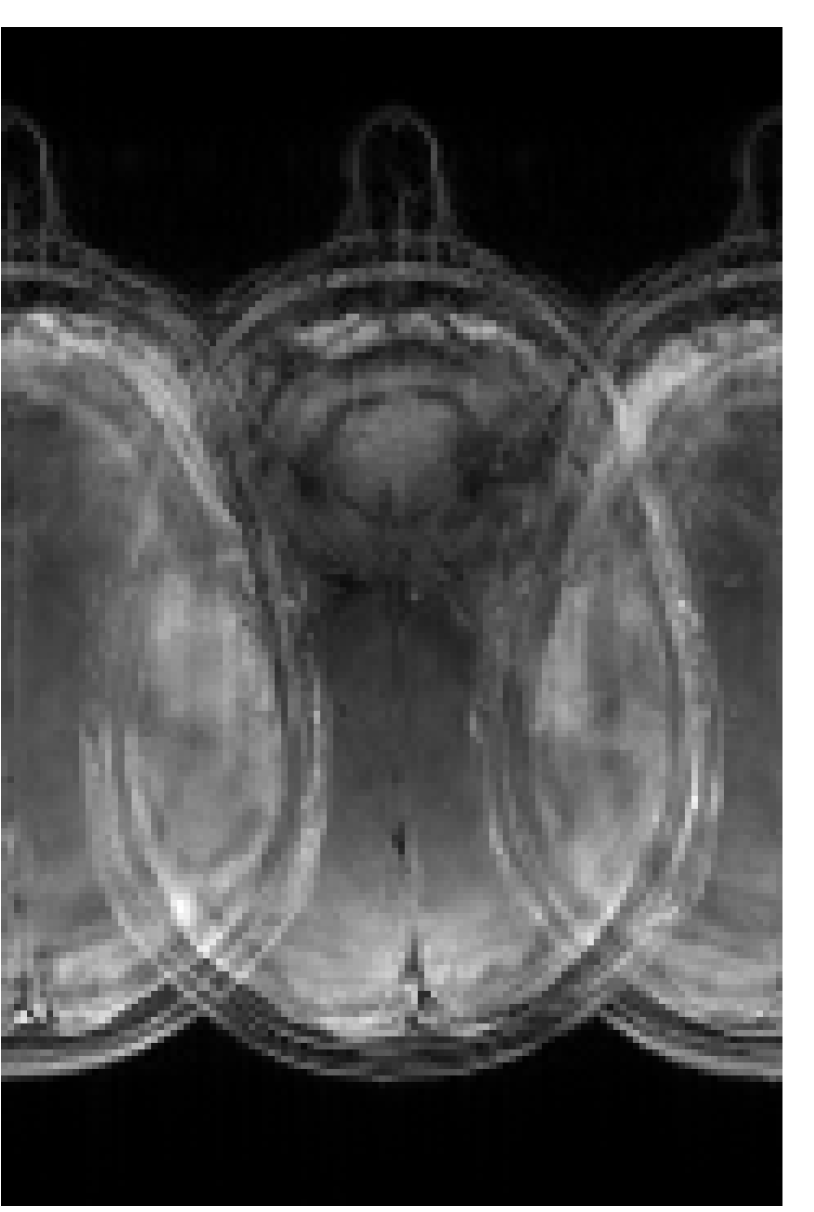

Figure 4 shows the results of the design of RF pulses for simultaneous excitation of two, four and six equidistant slices with a separation of and a thickness ; see Fig. 1(b). The computational effort in all cases is similar to that in the single-slice case. The corresponding computed pulses are shown in Figs. 4(a) to LABEL:sub@fig:sms:a6. A graphical analysis shows that instead of higher amplitudes, the optimization distributes the total RF power (which increases with the number of slices) more uniformly over the pulse length. A central section of the corresponding optimized slice profiles are given in Figs. 4(d) to LABEL:sub@fig:sms:b6. It can be seen that all slices have a sharp profile which does not deteriorate as the number of slices increases (although it decreases slightly farther from the center and the bandwidth is slightly reduced). These results are validated by the experimental phantom measurements using the computed pulses: Figs. 4(g) to LABEL:sub@fig:sms:c6 show the reconstructed excitation inside the phantom, while Figs. 4(j) to LABEL:sub@fig:sms:d6 show the measured slice profiles along a cut parallel to the -axis in the center of the previous images.

Figure 6 shows the image reconstruction using optimized RF pulses for simultaneous excitation of two, four and six slices with the same slice separation and thickness as above. As can be seen clearly in the first column, all three pulses lead to the desired excitation pattern in-vivo as well. The remaining columns show the slice-GRAPPA reconstructions, which illustrate that the excitation is uniform across the field of view.